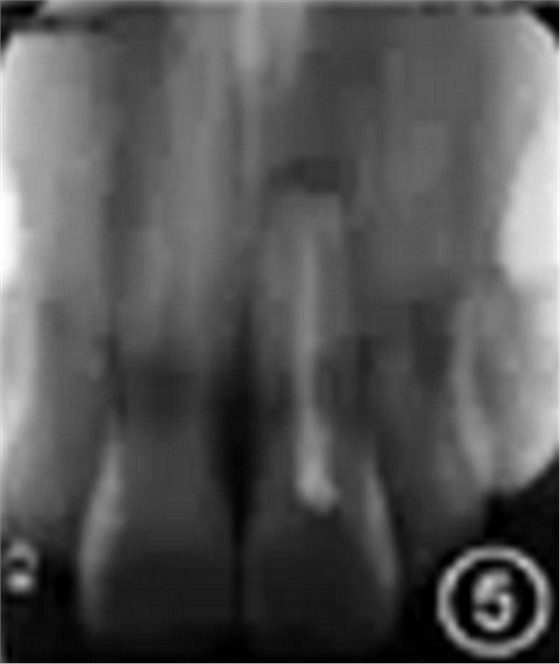

根尖X线片示根管中部以上可见高密度桩核影像,根充欠填,根尖有外吸收,根尖周低密度影。根管中上段无明显显影,结合临床检查判断为纤维桩,根充欠填,根尖周未见明显低密度影(图3)。锥形束CT显示根尖约4 mm×3 mm透影区,根尖部唇侧骨板缺损。根尖可见约1 mm×2 mm透影区,唇侧骨板完整(图4)。根尖未见明显低密度影。1年前根尖X线片显示根充欠填,根尖低密度影,牙冠完整,根尖无异常(图5)。

图5 患者1年前根尖X线片显示根充欠填,根尖低密度影,牙冠完整,根尖无异常